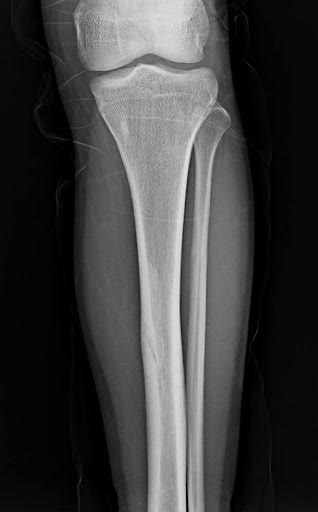

A 66-year-old male with right anterior elbow pain, ecchymosis, and a “lump” in his right upper extremity after a ground level fall.